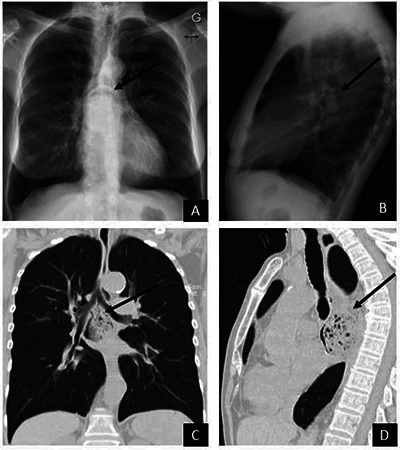

The air crescent (AC) is a common radiological sign. Even if its commonest aetiology remains pulmonary aspergillosis, various other causes have been described. In this study, we report four rare causes of ACs seen on chest radiographs that haven't been described in the literature. Teaching point: The differential diagnosis of an air crescent sign on chest radiographs includes oesophageal bezoar, interstitial lung emphysema, central bronchial stenosis and perforated emphysematous cholecystitis.

空气新月(AC)是一种常见的放射学征象。尽管其最常见的病因仍然是肺曲霉菌病,但也有其他各种病因的描述。在本研究中,我们报告了四种罕见的导致胸片上出现空气新月征的病因,这些病因在文献中还没有出现过。教学要点:胸片上出现气新月征的鉴别诊断包括食道大泡、肺间质气肿、中央支气管狭窄和穿孔性气肿性胆囊炎。